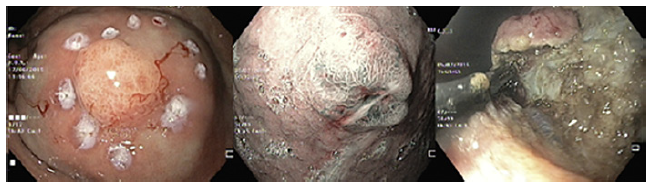

Standard EMR (EMRs) was defined as the conventional tech-nique of tumor resection with hot snare technique after submucosal injection with normal saline and diluted adrenaline (1:10,000 to 1:50,000 dilution) (Fig. 2). EMRc was performed with a transparent cap (Olympus, reusable oblique cap) at the tip of conventional upper GI endoscope and a crescent-type snare (EMR snare, Olympus). Hotsnare resection was done after submucosal injec-tion with normal saline and diluted adrenaline (1:10,000 to 1:50,000 dilution) and suction of the lesion into the cap. ESD was performed as previously described (Fig. 3). Briefly, small coagulation marks were made around the lesion and then submucosal injection was performed with saline, diluted epinephrine (1:50-100,000), and methylene blue. After elevation, 3-4 incisions were made with a needle knife (Olympus®) to get access to the submucosal layer, and an insulated-tip knife (mainly IT-KnifeTM; Olympus®) was used to perform circumferential dissection using the Endo Cut mode (Olympus electrosurgical unit, 80/60 W). Complete dissection was then performed in the Endo Cut or swift coagulation mode, with additional submucosal injection whenever necessary. The procedures were performed mainly under general anesthesia (with orotracheal intubation); deep sedation was restricted to a minority of procedures.